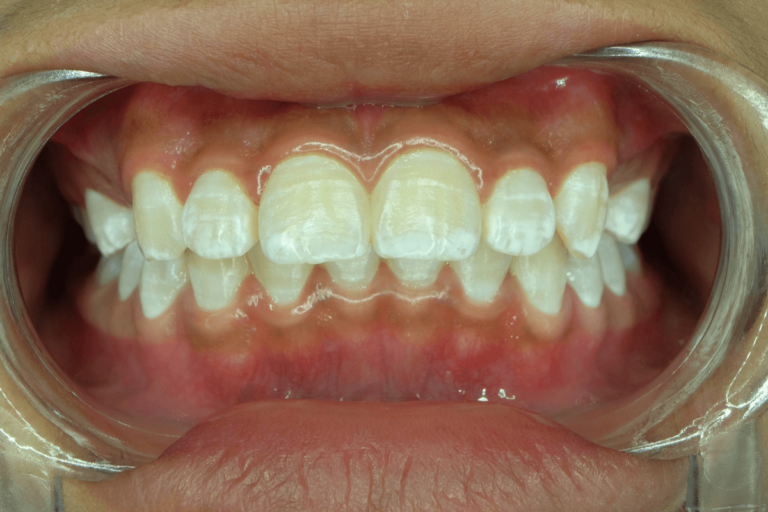

5. Manchas blancas asociadas al uso de ortodoncia

Existe una relación entre los tratamientos de ortodoncia con brackets y las manchas blancas en los dientes. Si bien no son los aparatos los que ocasionan estos defectos en las piezas dentarias, la dificultad para mantener una adecuada higiene dental suele dar origen a la afección

Al no higienizar de manera correcta todas las zonas de la boca se acumula placa bacteriana alrededor de los brackets y debajo de las bandas. Esto da lugar a una desmineralización del esmalte que se observa como manchas blancas en los dientes. En general, las mismas se hacen evidentes al retirar la aparatología y se deben tratar en ese momento.